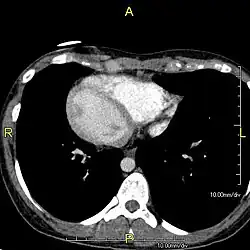

Diagnosis of situs inversus can be made using imaging techniques such as x-ray, ultrasound, CT scan, and magnetic resonance imaging (MRI).[9]

The condition affects all major structures within the thorax and abdomen. Generally, the organs are simply transposed through the sagittal plane. The heart is located on the right side of the thorax, the stomach and spleen on the right side of the abdomen and the liver and gall bladder on the left side. The heart's normal right atrium occurs on the left, and the left atrium is on the right. The lung anatomy is reversed and the left lung has three lobes while the right lung has two lobes. The intestines and other internal structures are also reversed from the normal, and the blood vessels, nerves, and lymphatics are also transposed.

If the heart is swapped to the right side of the thorax, it is known as "situs inversus with dextrocardia" or "situs inversus totalis". If the heart remains on the normal left side of the thorax, a much rarer condition (1 in 2,000,000 of the general population), it is known as "situs inversus with levocardia" or "situs inversus incompletus".